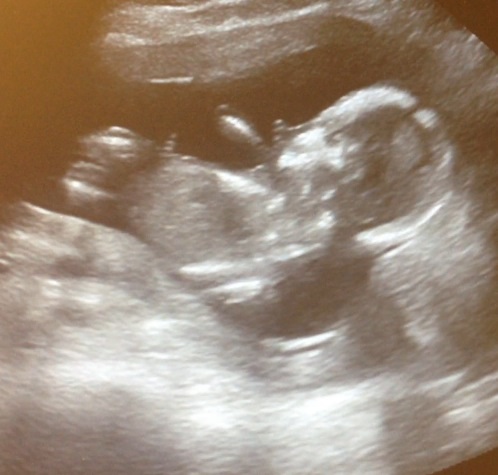

It's the same baby just different pictures, at different angles

If I really zoom into the bottom picture my guess would be girl

GIRL